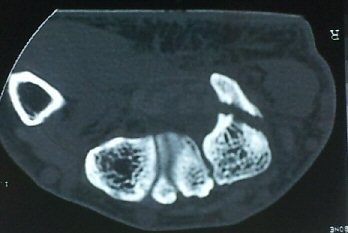

ÄÄÇ»ÅÍ ÃÔ¿µ»ó °¥°í¸®»À °¥°í¸® °ñÀýÀ» º¸ÀÓ(±×¸² 5, 6, 7).